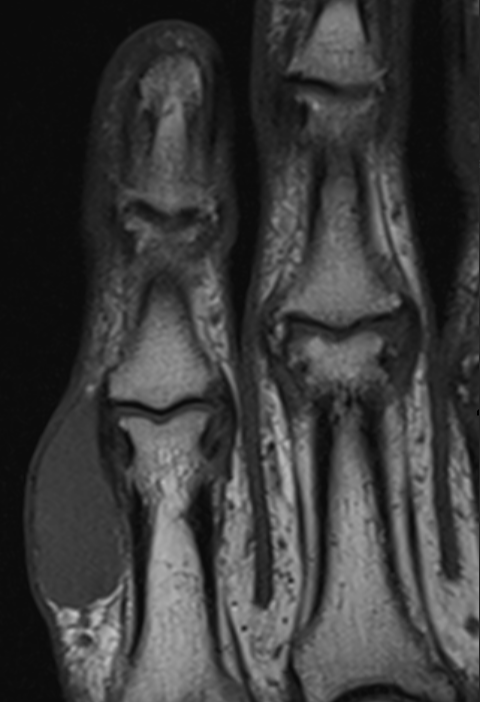

3. Giant cell tumor of tendon sheath